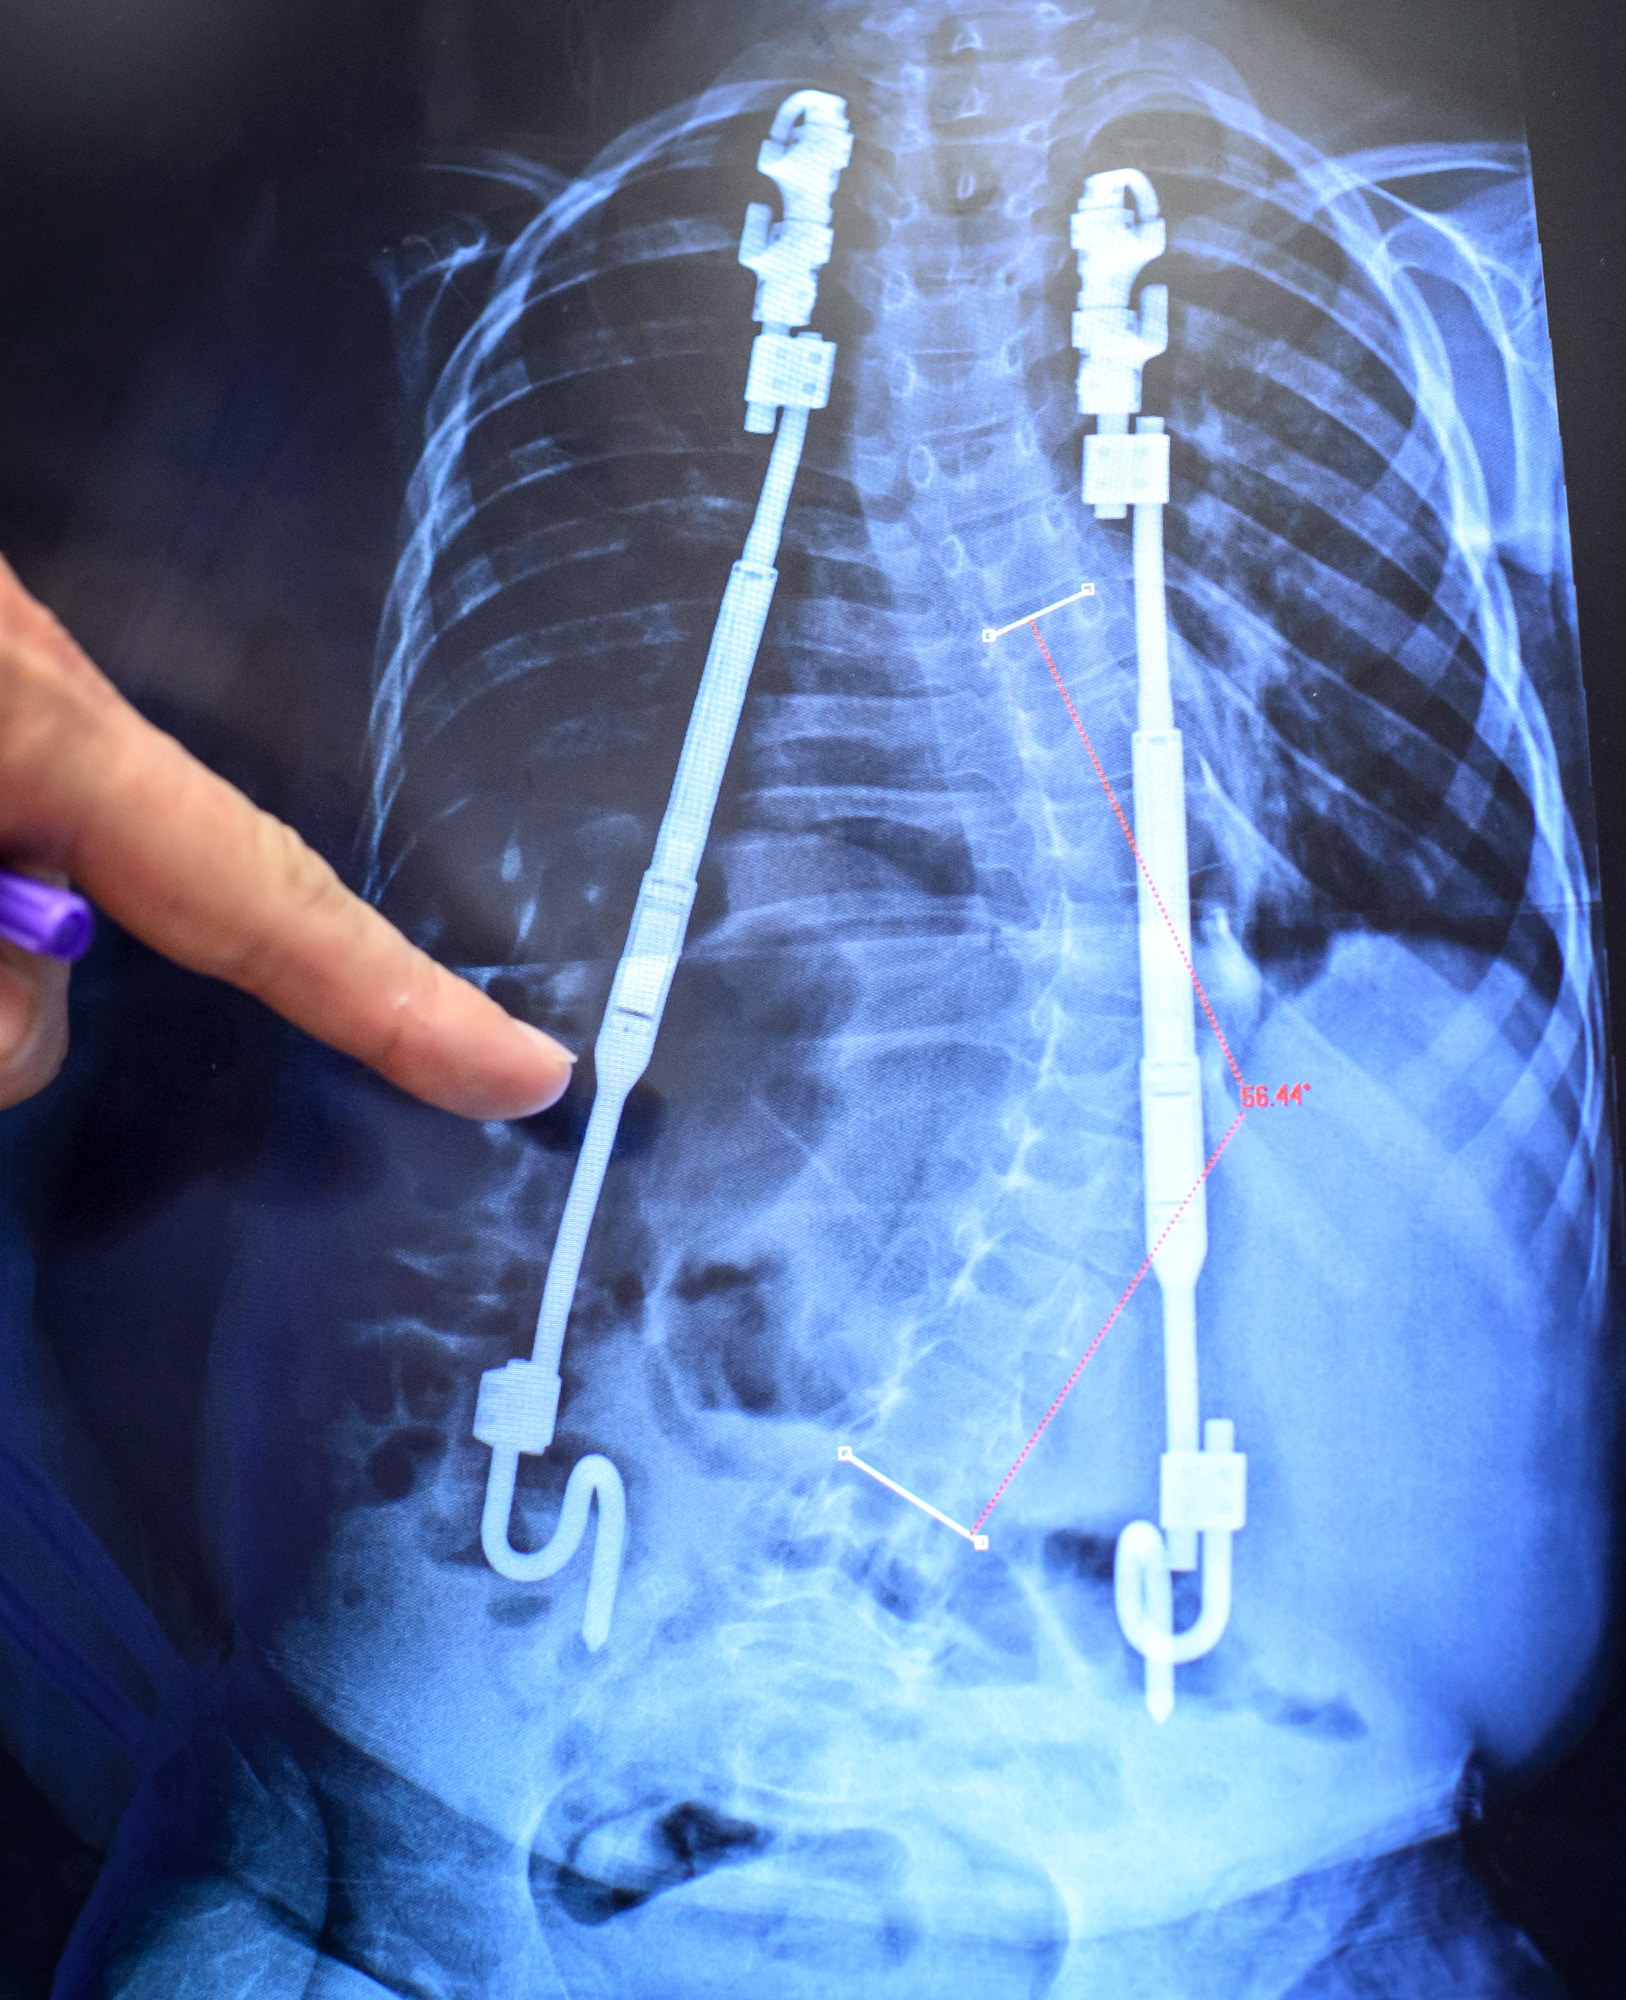

Plain radiographs of four MAGEC rods showing an intact internal Magec Rod Lengthening and the magec rod is typically lengthened or shortened as controlled by the doctor. The rod distractions allow the doctor to drive. with the magec system for rod lengthening, the number of surgeries is greatly reduced. — the magec system comprises a magnetically distractible spinal rod implant and an external remote. — magec is an evolving. Magec Rod Lengthening.

Scoliosis X Ray With Rods Magec Rod Lengthening — the magec system comprises a magnetically distractible spinal rod implant and an external remote. with the magec system for rod lengthening, the number of surgeries is greatly reduced. and the magec rod is typically lengthened or shortened as controlled by the doctor. The rod distractions allow the doctor to drive. — magec is an evolving. Magec Rod Lengthening.